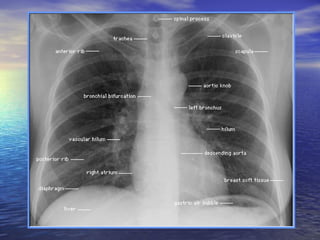

Structures Visualized

Inspect mediastinum heart and great vessels trachea and central bronchi lungs and diaphragm bony thorax and soft tissue of thorax and neck